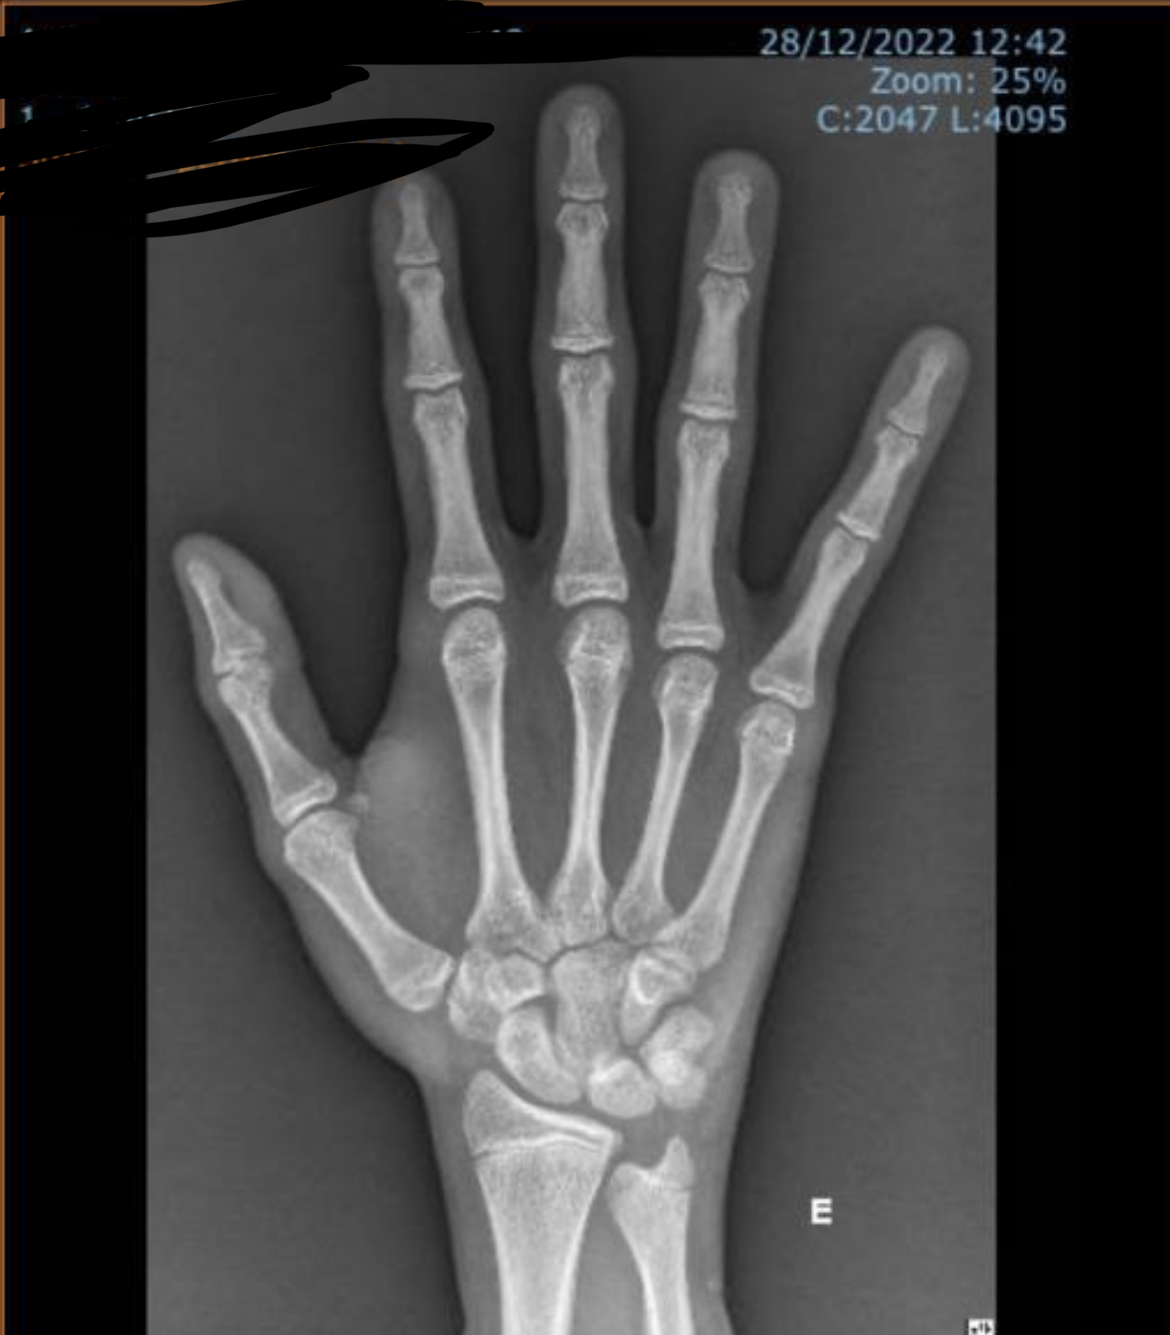

photo of hand x ray:

Judging by this X-ray. You’ll be around 180-183 By age 20. Maybe 185 if you grow after 20.

I can see the open growth plate on your radius